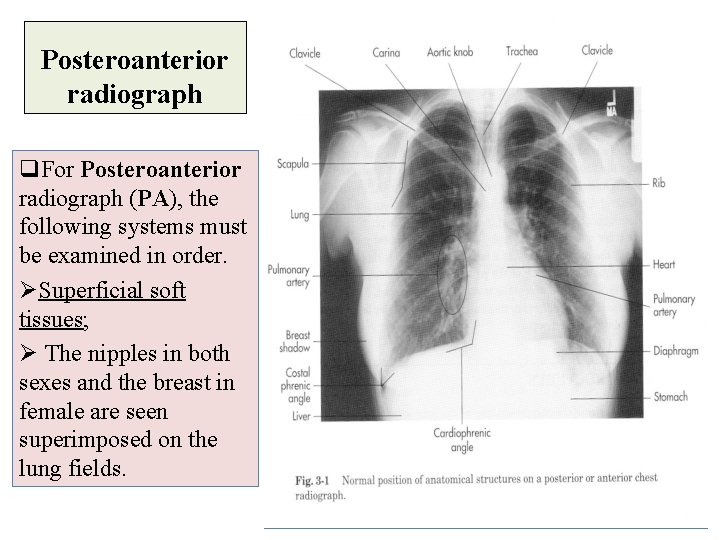

Posteroanterior radiograph q. For Posteroanterior radiograph (PA), the following systems must be examined in order. ØSuperficial soft tissues; Ø The nipples in both sexes and the breast in female are seen superimposed on the lung fields.

Posteroanterior radiograph (Bones) Bones of the thoracic cage, e. g. Ø (anterior ribs, posterior ribs). ØThoracic vertebrae. ØCost-transverse joints. ØClavicles. ØMedial border of the scapula.